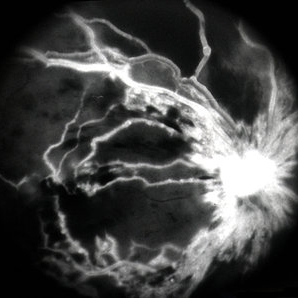

CRVO ischemic - FA 3

Jan 11 2013 by Alex P. Hunyor, MD

Severely ischaemic central retinal vein obstruction (CRVO), right eye - late phase fluorescein angiogram.

Condition/keywords: ischemic CRVO